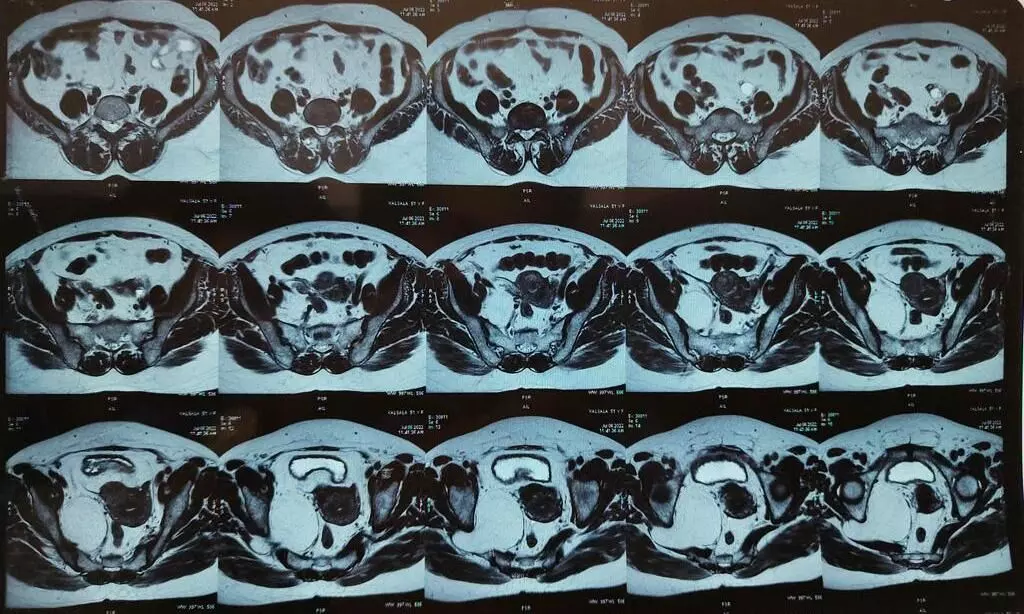

text_fieldsട്യൂമറിന്റെ സി.ടി. സ്കാനിൽ തെളിഞ്ഞ ചിത്രം

തിരുവനന്തപുരം: ട്യൂമർ നീക്കം ചെയ്യുന്നതിനായുള്ളലോകത്തെ ഏഴാമത്തേതും അത്യപൂർവവുമായ ഉദര ശസ്ത്രക്രിയ മെഡിക്കൽ കോളേജ് ആശുപത്രിയിൽ വിജയകരമായി പൂർത്തീകരിച്ചു. കഠിന വയറുവേദനയെ തുടർന്ന് ആശുപത്രിയിലെത്തിയ 48 കാരിയായ രോഗിക്കാണ് ശസ്ത്രക്രിയ നടത്തിയത്. പരിശോധനയിൽ ശരീരത്തിന്റെ പിൻഭാഗത്ത് ഇടുപ്പ് ഭാഗത്തെ കവാടമായ സയാറ്റിക് ഫൊറാമനിലൂടെ തള്ളി വരുന്ന മുഴയാണ് രോഗകാരണമെന്ന് കണ്ടെത്തി.

വെള്ളിയാഴ്ചയാണ് ശസ്ത്രക്രിയ നടന്നത്. കാലിന്റെ ചലന ശേഷിയിൽ സുപ്രധാന പങ്ക് വഹിക്കുന്ന ഞരമ്പായ ഷിയാറ്റിക് നെർവിനോടു ചേർന്നാണ് മുഴ സ്ഥിതി ചെയ്തിരുന്നത്. ഞരമ്പിന് കേടു പറ്റാതെ അതീവ ജാഗ്രതയോടെയാണ് സർജറി നടന്നത്. ട്യൂമറിനെ രണ്ടായി മുറിച്ചാണ് പുറത്തെടുത്തത്. എട്ടുമണിക്കൂർ സമയമെടുത്താണ് ശസ്ത്രക്രിയ നടത്തിയത്.

ജനറൽ സർജറി വിഭാഗത്തിലെ ഡോക്ടർമാർ ഗ്ലൂട്ടിയൽ ലൈപ്പോ സാർക്കോമാ ഹെർണിയേറ്റിംഗ് ത്രൂ സയാറ്റിക് ഫൊറാമൻ എന്ന പേരിലറിയപ്പെടുന്ന ലോകത്തെ ഏഴാമത്തെ ശസ്ത്രക്രിയയിലൂടെ മുഴ നീക്കം ചെയ്യുകയായിരുന്നു. വയറിന്റെ ഉൾഭാഗവും തുടയുടെ മുകൾ ഭാഗവും തുറന്നാണ് മുഴ പുറത്തെടുത്തത്. രോഗി സുഖം പ്രാപിച്ചുവരുന്നു.